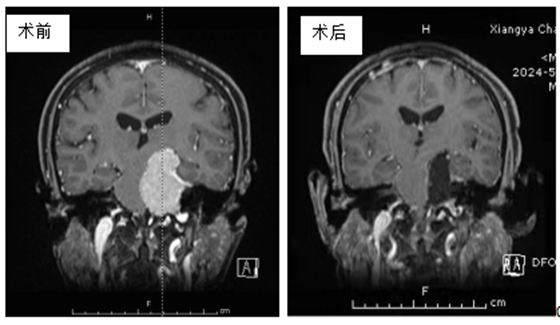

来自江西上饶市的朱女士,近7年来反复出现左耳耳鸣伴听力下降,耳鸣表现为“轰轰轰”声,当时未予以重视,以为就是单纯的年纪大了才出现的一些症状,直到近日因头晕加重,前往当地医院就诊,头颅MRI示:左侧桥小脑角区占位性病变,约53mm*27mm大小,考虑脑膜瘤可能。为求进一步诊疗,朱女士在家属陪伴下慕名来到湘雅常德医院找袁贤瑞教授看诊。

手术当日,袁贤瑞教授带领的以姜尚军副主任医师为主的医疗团队与麻醉医师及手术护士密切配合,在显微镜下,袁贤瑞教授团队以娴熟高超的技术将蝶岩斜区5.5*4*5cm拳头大小的肿瘤全切,患者颅内大血管未见明显损伤,重要颅神经功能保护完好。